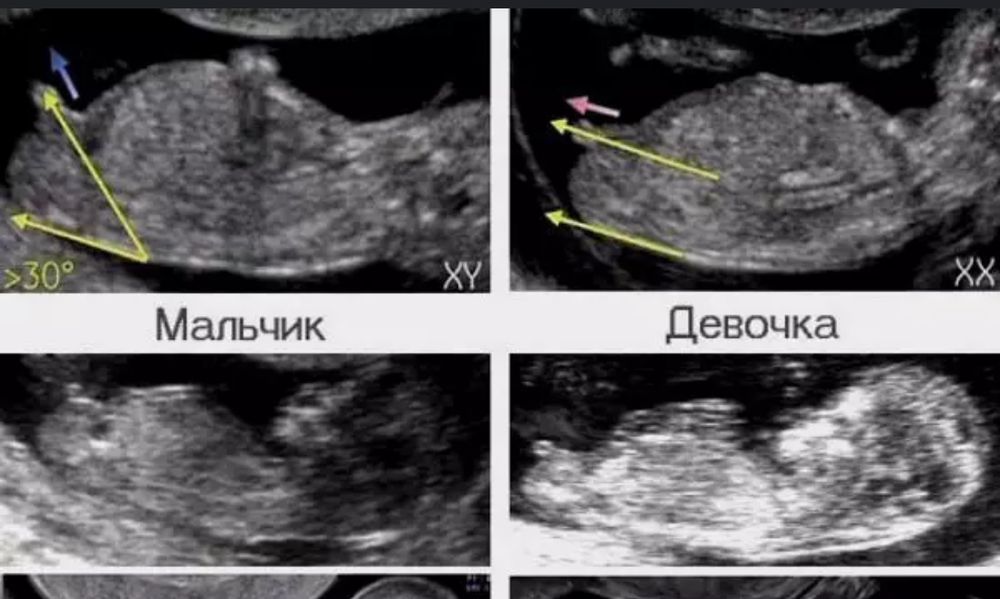

Здесь можно только гадать, ничего не видно и рано еще для четкого определения пола.

Качество и правда ужасное, сомневаюсь что кто то что то раз глядит , сдайте лучше кровь на определение пола или подождите пару недель , моей дочери пол смогли увидеть только на 15 неделе и то на узи была почти два часа ибо пряталась , хорошо врач в платной клинике была упертая 😃🙏

ЗеЛеНоГлАзКа, отказалась скорее всего потому что плохо видно , и может быть ложный ответ , мне кажется никому на первом скрининге не говорят пол, на втором может быть и то не всегда , мне допустим отказались говорить на втором скрининге тк ребенок не удачно лежал и было не видно , и как мне ответили это не в их интересах , они смотрят на развитие , спасение в мою беременность было только платное узи , тк только там будут с вами возиться, а в бесплатной за вами еще очередь стоит

Мне кажется больше на мальчика похож ❤️